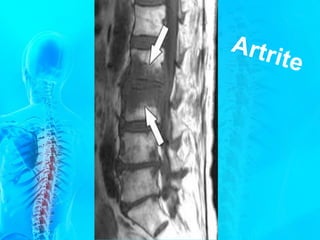

COLUNA VERTEBRAL

É a estrutura que sustenta nossa

posição bípede, e por isso, talvez a mais

sacrificada na escalada do desenvolvimento

humano.

A curvatura lombar, geralmente mais acentuada nas

mulheres, termina no ângulo lombo-sacral. A curvatura

sacral também se difere nas mulheres, menos curvo

nestas, o que aumenta o tamanho da abertura inferior da

pelve ou saída da pelve (pelve verdadeira).